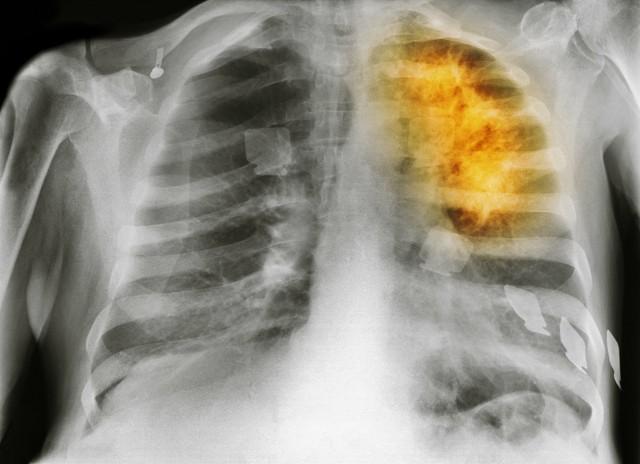

但第三个误区几乎所有人都在犯:只盯着肺部CT,却忽视了血液指标的变化。一个真实案例:66岁的王阿姨,咳嗽两年了,一直做胸片,啥也没查出来。直到有一天走路都喘,查血发现白蛋白掉得厉害、炎症指标飙升,再一查PET,肿瘤已扩散肝脏。

你可能不信,肺癌晚期病人中,超过60%的人,最后是因为感染或器官衰竭去世的。比如肺部感染、肝功能衰竭、脑水肿。这才是“压死骆驼的最后一根稻草”。